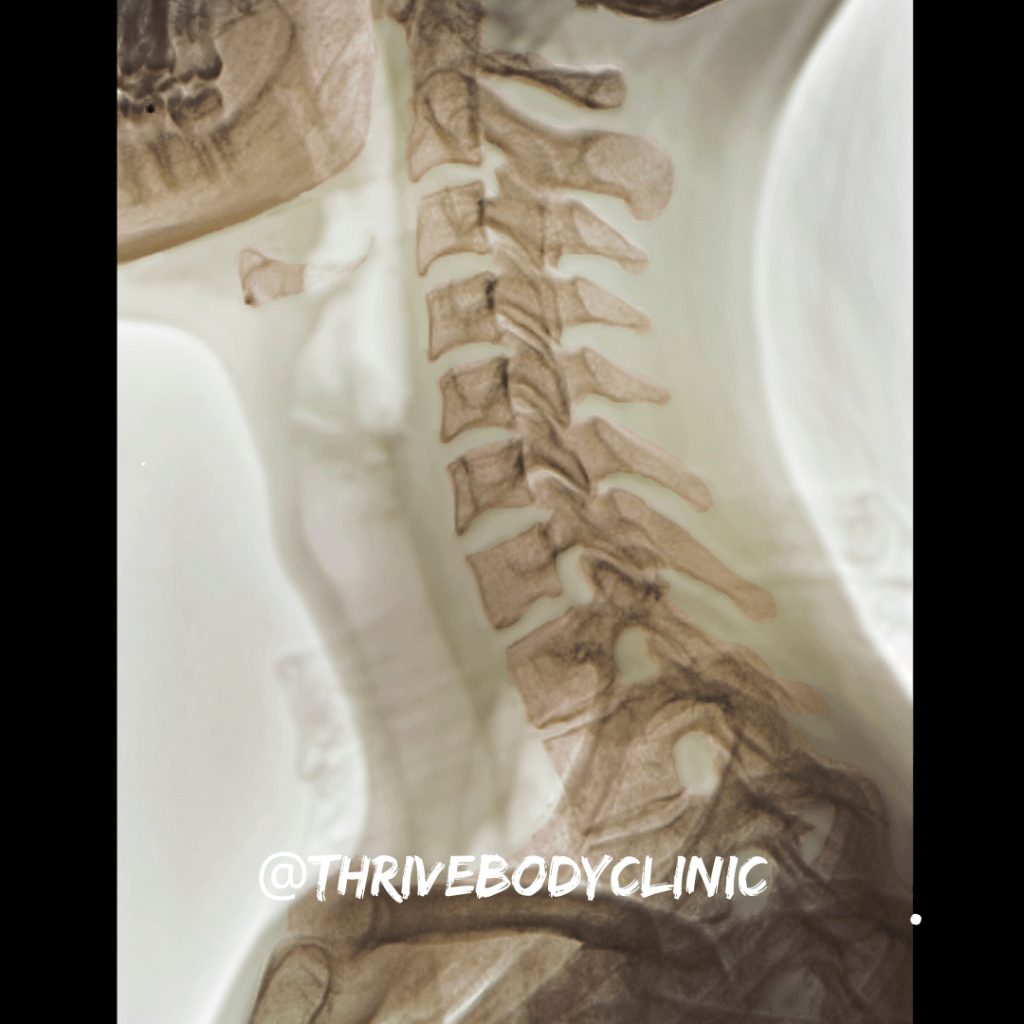

Your spine is a marvel of engineering, designed to provide strength, stability, and flexibility. Running down the back of your body, the spine is made up of 24 vertebrae that interlock like a chain. Between each of these vertebrae are facet joints, which allow the spine to move smoothly in various directions.

Facet joints are small, bony projections at the back of each vertebra. They’re covered with cartilage, a smooth tissue that reduces friction and enables easy movement. Surrounding each facet joint is a capsule filled with synovial fluid, which lubricates the joint and helps maintain its range of motion. These joints play a critical role in supporting and guiding the movement of your spine, allowing you to bend, twist, and extend your back and neck.